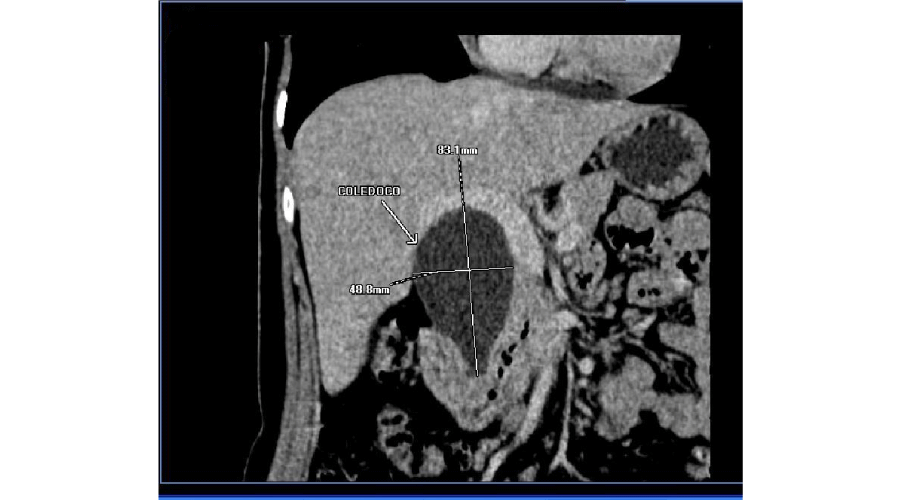

After this primary diagnosis, she was underwent an abdominal CT, which showed a fluid formation of about 50mm in diameter, extending for about 70mm along the choledochus, morphologically compatible with type I b choledochal cyst. CT revealed no gallstones within the common bile duct and no thickening wall of the common bile duct; the pancreas had regular morphology, and no dilatation of the Wirsung duct. A 60x40mm cyst was detected on the right ovary.

The MRCP confirmed the presence of a cyst of the bile duct, classified type I, sized 60x42mm; the choledochus was dilatated, without endoluminal gallstones; there was no expansion of the intrahepatic ducts; gallbladder sludge was present and microlithiasis. The main pancreatic duct was regular and no focal pancreatic lesions were detected (Figure 1).

Figure 1: